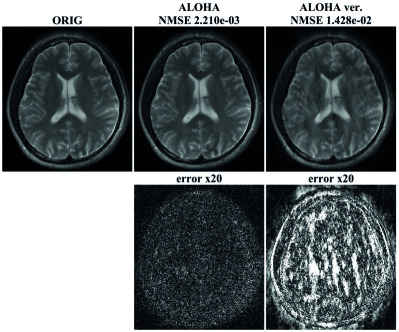

When generalizing the Hankel matrix model from single to multiple channels, we chose to stack the Hankel matrices corresponding to individual channels side by side. One could suggest stacking them one on top of another, which would represent a different matricization. Based on our discussion in Section II, in order to stack the Hankel matrix on top of another, the Hankel matrices should share the same annihilating filter. However, for the TV signal, the structure in (62) showed that it is not possible to find a common annihilating filter such that On the other hand, the relationship in Eq. (63) clearly showed that there are inter-coil annihilating filters that can cancel out each combinations of the k-space signals. Therefore, to utilize (63), we should stack the Hankel matrix size by side.

To confirm the theoretical findings, we compared the reconstruction results from the two different stacking of Hankel matrices. As shown in Fig. 8, the vertical augmentation of Hankel matrices provided inferior reconstruction results compred to the side by side augmentation of Hankel matrices. This again confirmed the importance of the concatenation direction and the analysis by Proposition 3.2.